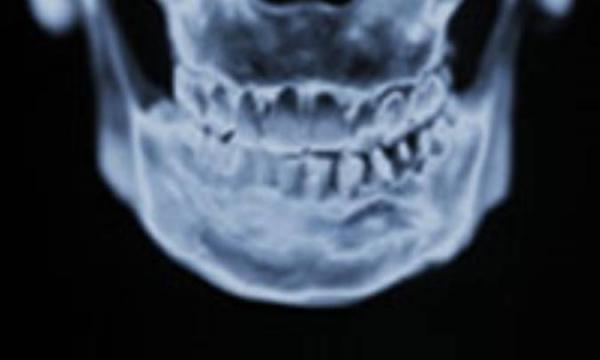

این سندرم به اسم یکى از پیچیده ترین و اختلاف برانگیزترین بیمارى هاى انسان امروزى است.

ما نمى خواهیم وارد این بحث اختلاف برانگیز شویم که TMJ یک اختلال عضلانى است یا استخوانى و غضروفى و یا اینکه دلیل اولیه ایجاد آن به دلیل فشار و استرس مى باشد یا دندان هاى نامرتب و یا هر مشکل دیگر.

علایم سندرم TMJ شامل سردرد، دندان درد، گردن درد و یا درد شانه و کمر درد و صداى تق تق هنگام باز کردن یا بستن فک است. اگر چه علایم دیگرى وجود دارند که شدیدترند و در صورت بروز باید از طریق دندان پزشک مورد بررسى قرار بگیرند. دکتر پرى مى گوید: اگر نمى توانید دهان را باز کنید و یا دندان ها را مسواک بزنید و سر دردهاى شدید دارید باید به پزشک مراجعه کنید.